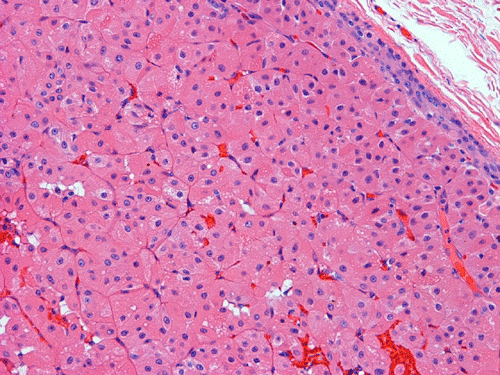

Clinical information: The patient is a 75-year-old white male, who was referred for evaluation of a right parotid mass, which was initially very difficult to assess clinically. An MRI was done at the referring institution, which showed 1 x 2 cm mass located in the mid portion of the superficial portion of parotid gland. The mass was removed by a parotidectomy and yielded the following images.

Pathology of the Case: Grossly, the tumor was a small 1 x 2 cm well demarcated nodule embedded within the mid portion of the salivary gland. There is no true capsule (Panel A). The tumor cells arrange in solid sheets and without specific pattern formation (Panel B and C). There is no collagenous tissue within the tumor. The tumor cells are polygonal and rather homogeneous in size. They have low-grade, centrally located nuclei (Panel D), finely granular and distinctly eosinophilic cytoplasm. The granular feature is best appreciated in the cytoplasmic preparation that is prepared while the tumor is being examined before fixation (Panel E). There is no necrosis or mitotic figures.

Grossly, oncocytomas are well-circumscribed, well-demarcated, round to lobulated nodules, averaging 3-4 cm in size. Oncocytomas arising from major salivary glands are usually encapsulated and those arising from minor salivary glands have less well defined borders and are usually not encapsulated. The cut surface has a typical tan-brown color. Benign oncocytomas frequently have with a central star-like scar.

Microscopically, oncocytes have a very characteristic appearance with granular eosinophilic cytoplasm due to marked increase in the number of mitochondria mitochondria, pleomorphism of mitochondria, and a paucity of other organelles. The tumor cells have little variation among different tumors or different part of the same tumor. Characteristically, the tumor cells are rather uniform and polygonal in shape. The cytoplasmic membrane can be readily recognized. The nuclei are usually round, centrally located, and nucleoli are present. The cells are arranged in uniform solid sheets without a specific pattern or they may aggregate into clusters, and sometimes they form duct-like structures. Thin fibrovascular septa are present. Oncocytomas may have a clear cell component secondary to accumulation of cytoplasmic glycogen 6. A PAS stain with and without diastase digestion will be very helpful in recognizing the glycogen. High grade nuclear atypia is only seen exceptionally. Phosphotungstic acid hematoxylin (PTAH) is a good stain that would stain the mitochondria dark. However, the stain is rarely called to service for this purpose as the cytoplasm is typically characteristic enough for recognition without special stain. In clear cell variants, however, PTAH may help. Mitotic figures are not readily seen. In most situations, the diagnosis of oncocytoma is not a particularly challenging one.